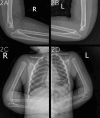

Figure 1. Chest and forearm plain radiographs.

Chest AP view (1A, top left); chest lateral view (1B, top right); forearms lateral view (1C, bottom center).